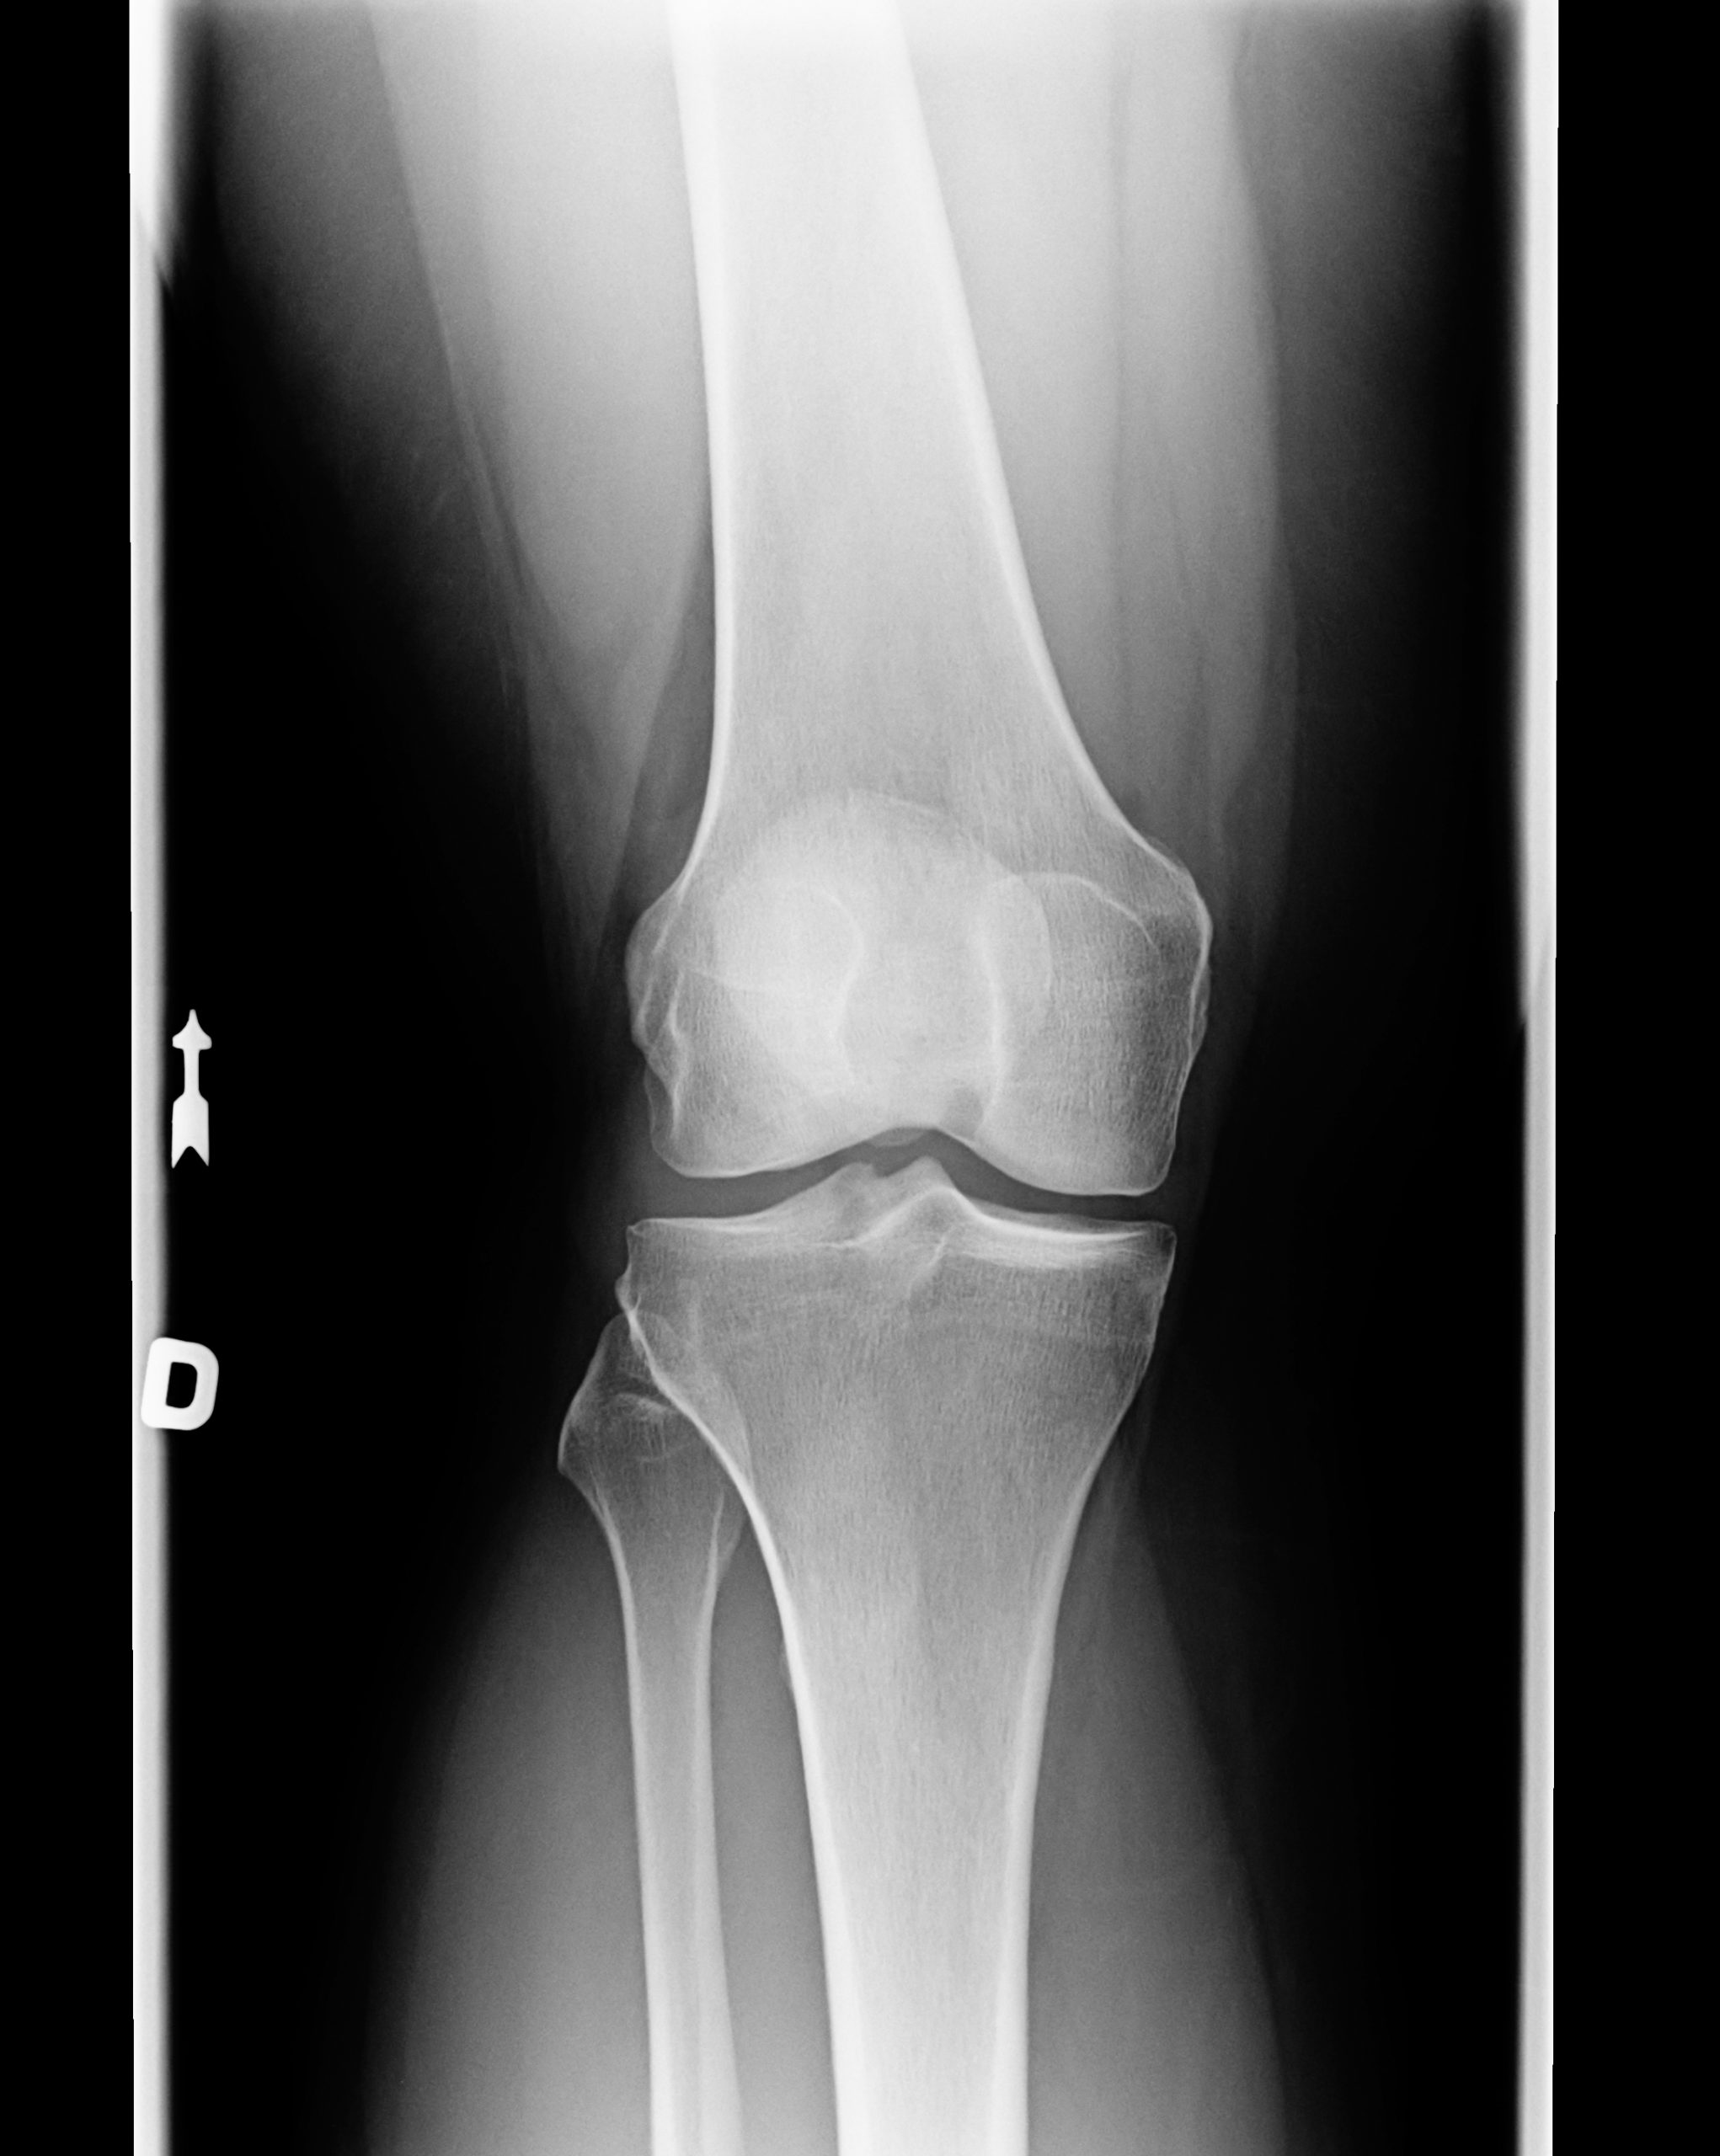

Knorpelschaden Knie Grad 4. Knie & Knorpelschaden OP ist nötig, um das Einheilen der Knorpelzellen zu ermöglichen Knorpelschaden Knie Grad 3: Risse im Knorpelgewebe, die über 50% der gesamten Knorpeldicke liegen und bis zum Knochen reichen können; Knorpelschaden Knie Grad 4: Die gesamte Knorpelschicht ist bis zum Knochen hin abgebaut, der Knochen liegt frei; konservativ.

Stadium der Kniearthrose liegen schwere Knorpelschäden vor. Knorpelschaden im Knie Grad 4 Die Knorpelschädigung des Grades 4 entspricht der stärksten Schädigung des Kniegelenkknorpels nach Outerbridge Bei Knorpelschaden hinter der Kniescheibe, kann es bei Fehlstellungen zusätzlich sinnvoll sein das seitliche Kniescheibenband zu lockern (laterales Release) das es zu einem besseren Zentrierung der Kniescheibe kommt und hiermit zu einem Verringerung des.

Knorpelschaden Knorpelbehandlung Arthrose KLINIK am RING. Ursachen sind Beinfehlstellungen, chronische Entzündungen oder Band- und Meniskusschäden. Grad 4: der Knorpelschaden zeigt den darunter liegenden (subchondralen) Knochen